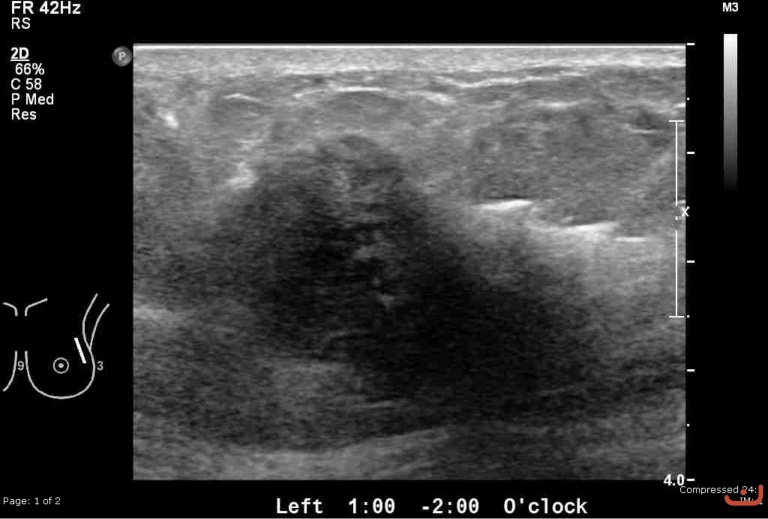

Malignant solid mass

Date

Thursday, 30 April 2015

174.16 KB (768 x 519 px)